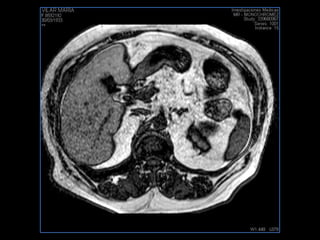

PROTOCOLO hígado graso AXIAL in phase y out phase AX T1 y AX fat sat +SAG T2  CON   GADOLINIO :  COR T1+AX T1(DIN) SAT: NO  FASE: RL THK: 4MM  COIL:  GAP: (FACTOR 1.4)  FOV: 40 CM NEX:2 SINCRONIZACION RESPIRATORIA EN 3 O 4 CICLOS ALE